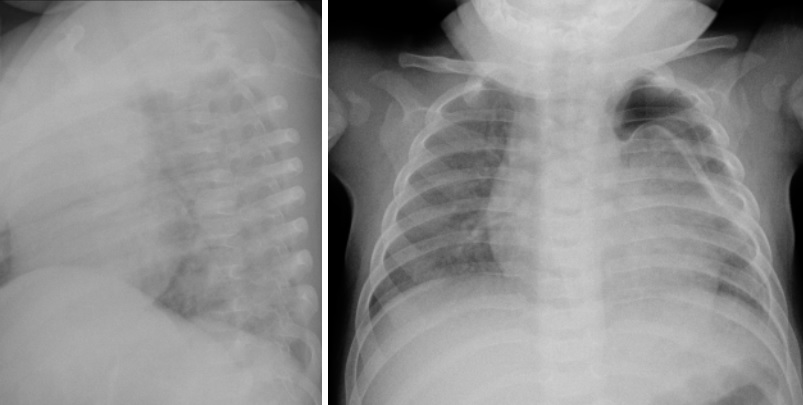

Imagens De Raio X Revelam Danos Da Sindrome Gerada Apos Covid 19 Em Criancas Revista Galileu Saude

revistagalileu.globo.com

Imagens Mostram Danos Do Coronavirus Causador Da Covid 19 Nos Pulmoes Revista Galileu Saude